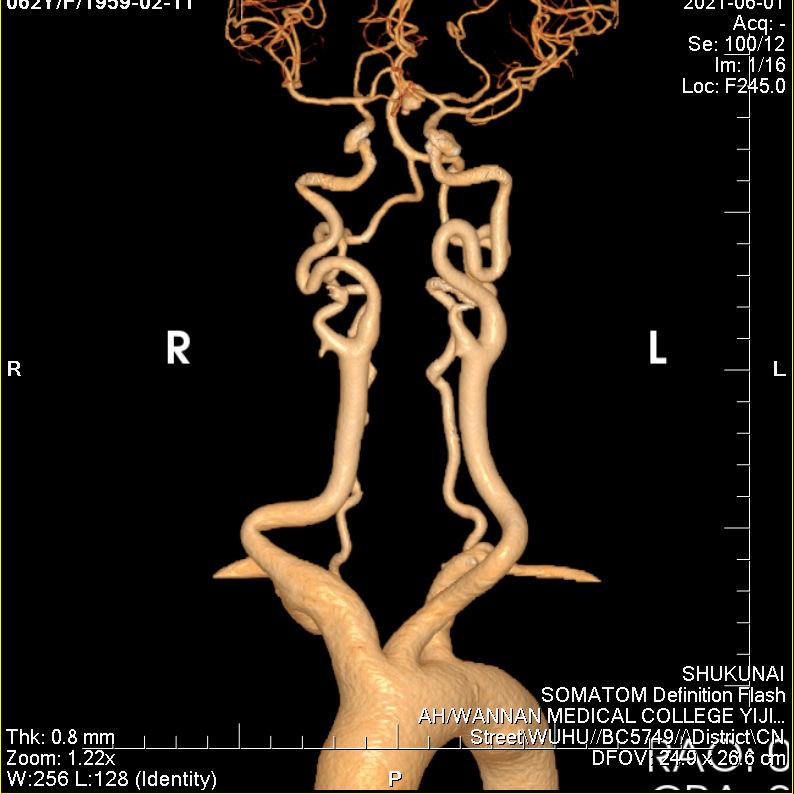

脑动脉CTA示左侧大脑中动脉M1段动脉瘤、左侧大脑后动脉P3段动脉瘤。

左侧颈动脉极度迂曲。

通桥银蛇®DA远端通路导引导管轻松至海绵窦段。